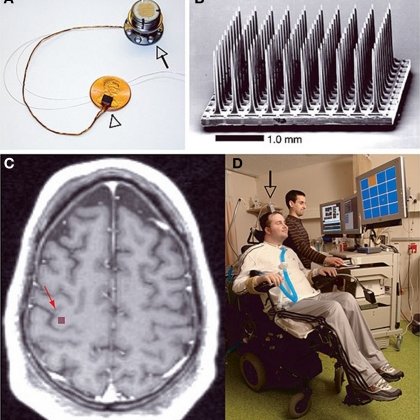

Quá trình tái hiện ký ức khi ngủ, hay offline replay, đã được các nhà khoa học ghi nhận trên động vật từ nhiều thập kỷ trước. Nhưng bởi các thí nghiệm này thường không an toàn cho con người, nên đến nay, nghiên cứu trên tạp chí Cell Report mới là lần đầu tiên offline replay được xác nhận một cách trực tiếp trên những tình nguyện viên hết sức đặc biệt – đó là hai người đã được cấy sẵn một vi điện cực vào trong não bộ.

Hai cá nhân tham gia vào thử nghiệm là những bệnh nhân mắc tetraplegia – một chứng liệt tứ chi khiến họ không thể cử động chân và tay của mình. Để giúp những người này giao tiếp được, một dự án nghiên cứu trước đó có tên gọi là Cổng não (BrainGate) đã cấy vào vỏ não vận động của họ một mảng vi điện cực nội sọ (microelectrode).

Các vi điện cực nội sọ này có thể ghi lại tín hiệu bắn ra từ nơron thần kinh của bệnh nhân, từ đó tái tạo chúng thành tín hiệu điện giúp điều khiển con trỏ chuột máy tính hoặc cử động của các cánh tay robot được kết nối với não bộ người bệnh.

Điều này đã khiến hai bệnh nhân tetraplegia trở thành đối tượng nghiên cứu hoàn hảo cho một thí nghiệm offline replay. Các nhà khoa học có thể ghi lại các tín hiệu noron thần kinh của họ trong khi thức giấc, và so sánh với tín hiệu phát ra trong khi họ ngủ thông qua vi điện cực nội sọ.